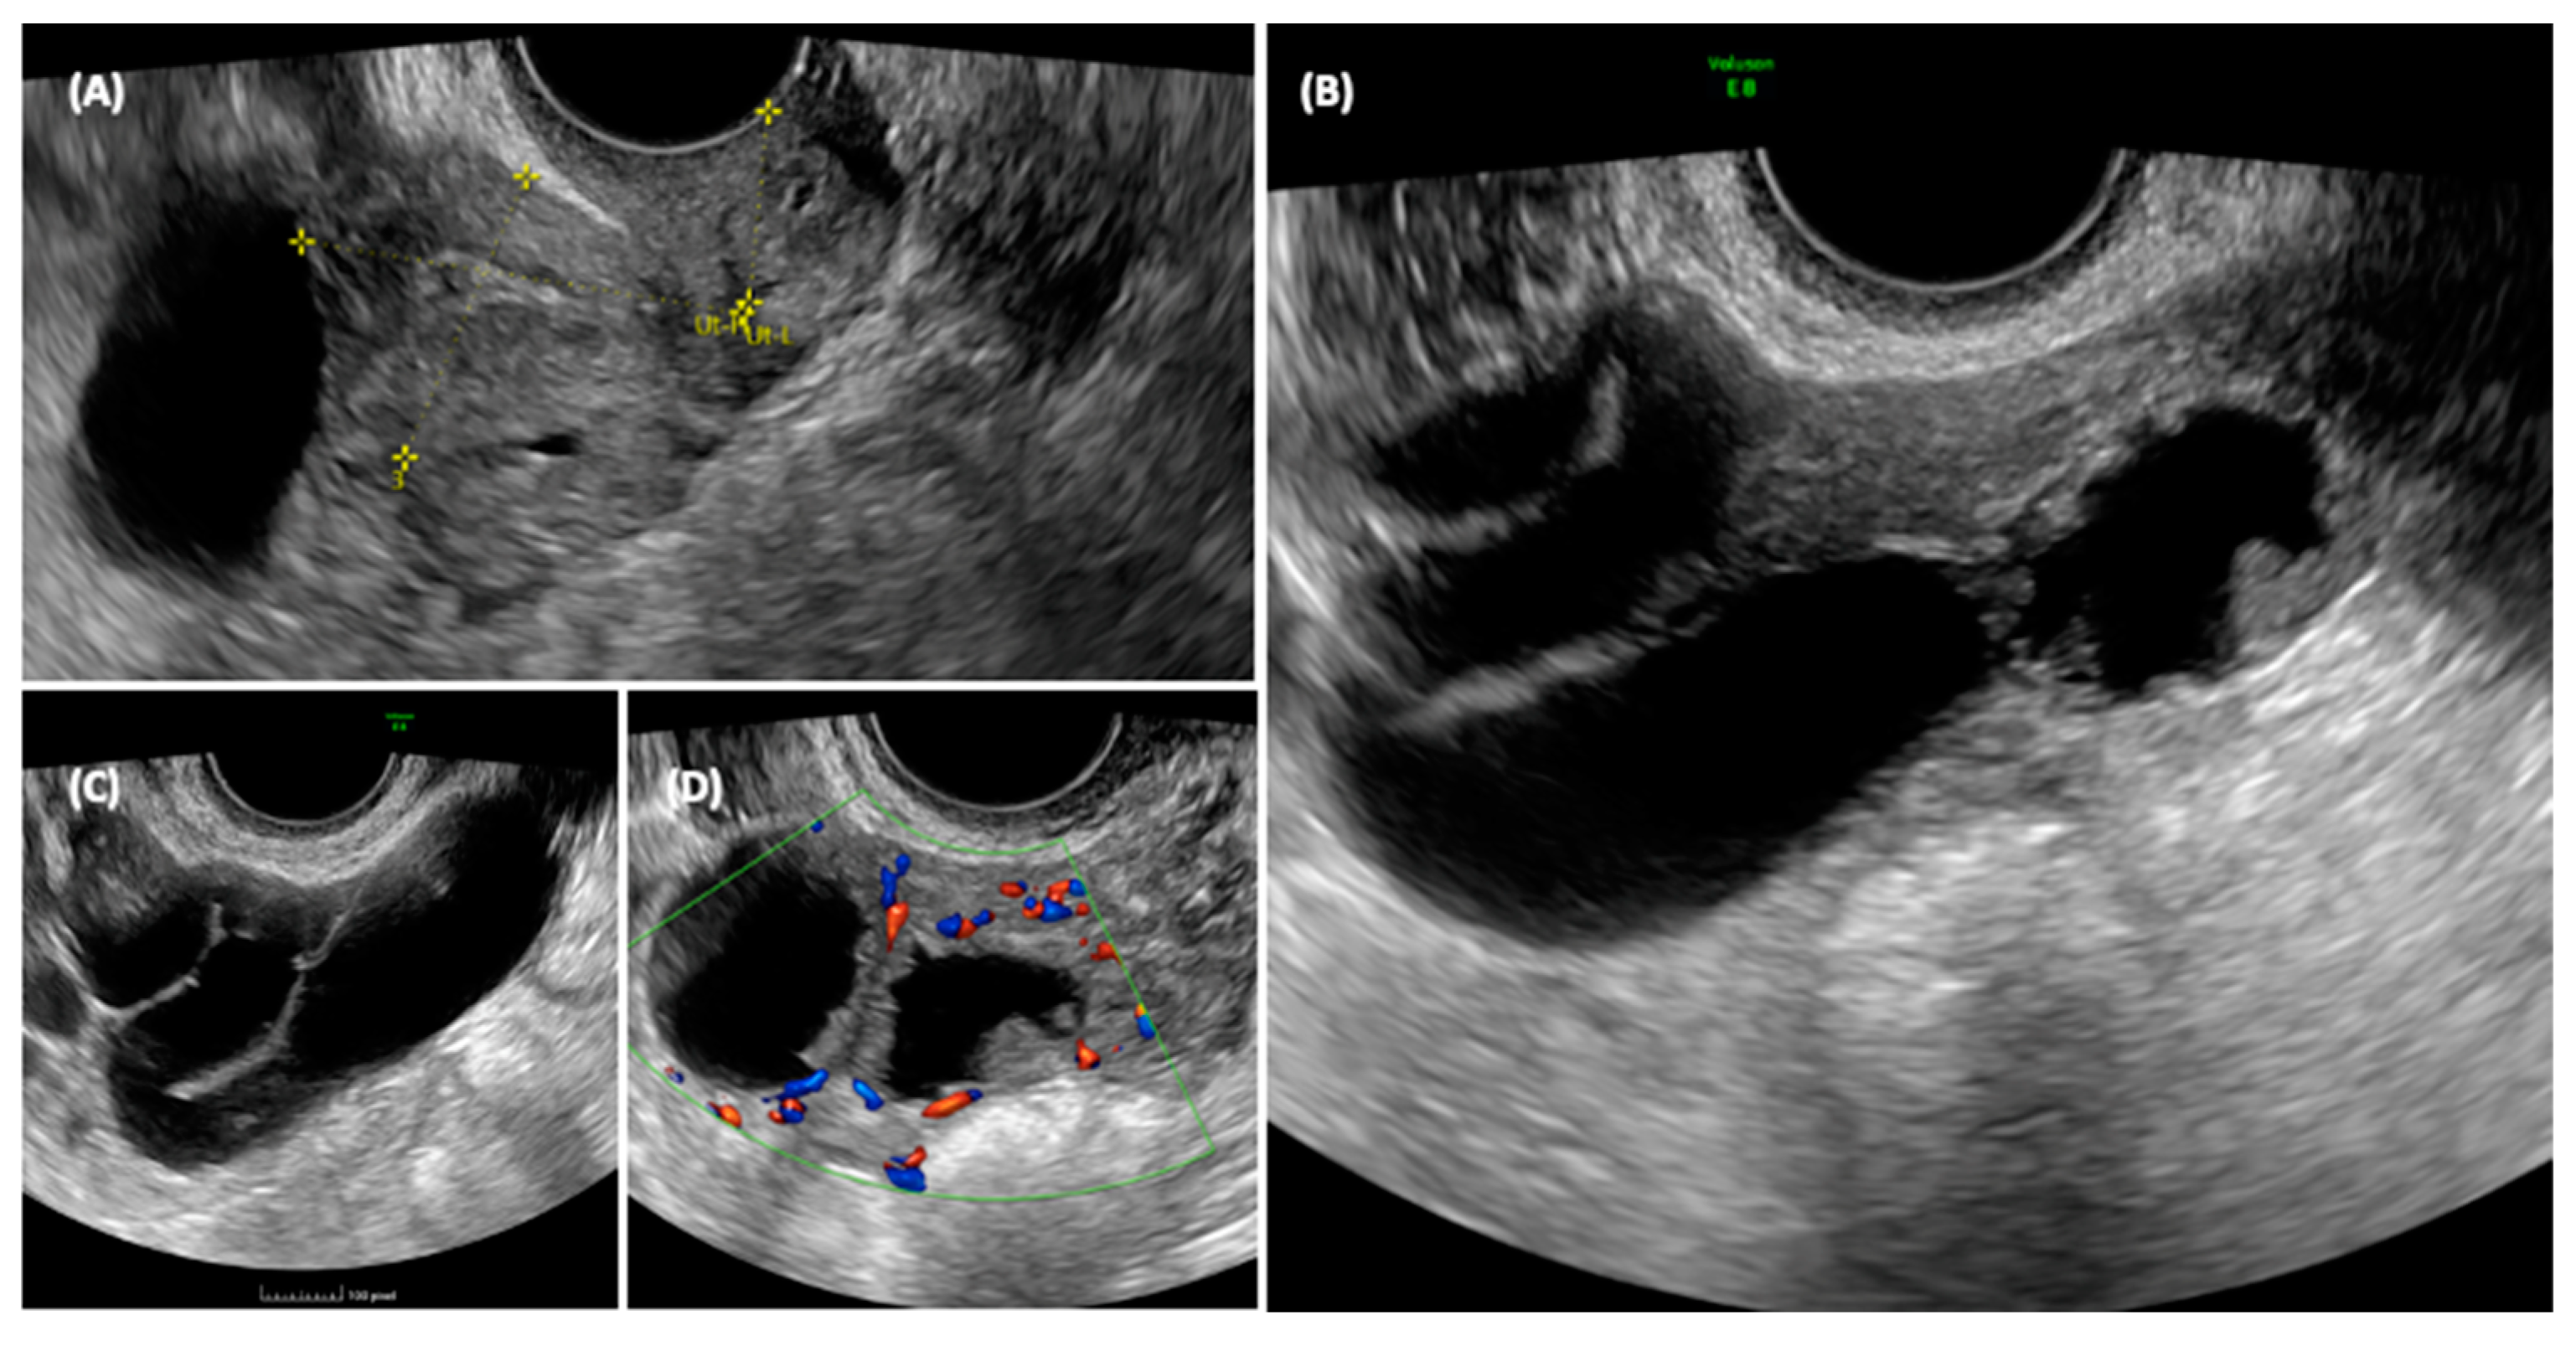

3.6.1. Case 1

3.6.2. Case 2